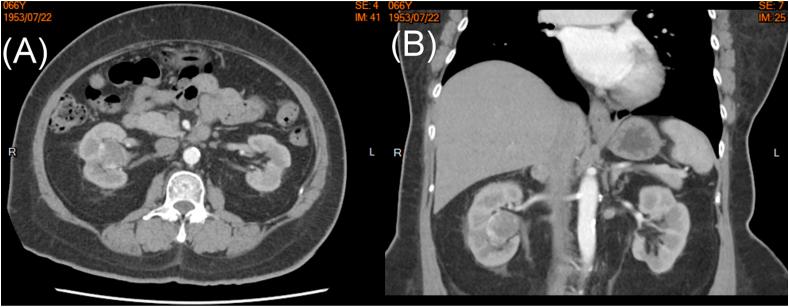

血管肉瘤(AS)是一种起源于内皮细胞的罕见侵袭性肿瘤。我们报告了一名66岁的原发性肾血管肉瘤(PRA)女性患者,其表现为血尿和排尿困难的尿路上皮癌。根据输尿管肾镜肿瘤活检,初步诊断为低级别非侵袭性尿路上皮癌。然而,肾输尿管切除术获取的标本确诊为原发性肾血管肉瘤。原发性肾血管肉瘤很少表现为肾盂尿路上皮癌。手术切除仍然是最有效的治疗方法,但关于辅助治疗尚无共识。原发性肾血管肉瘤的总体预后不佳。